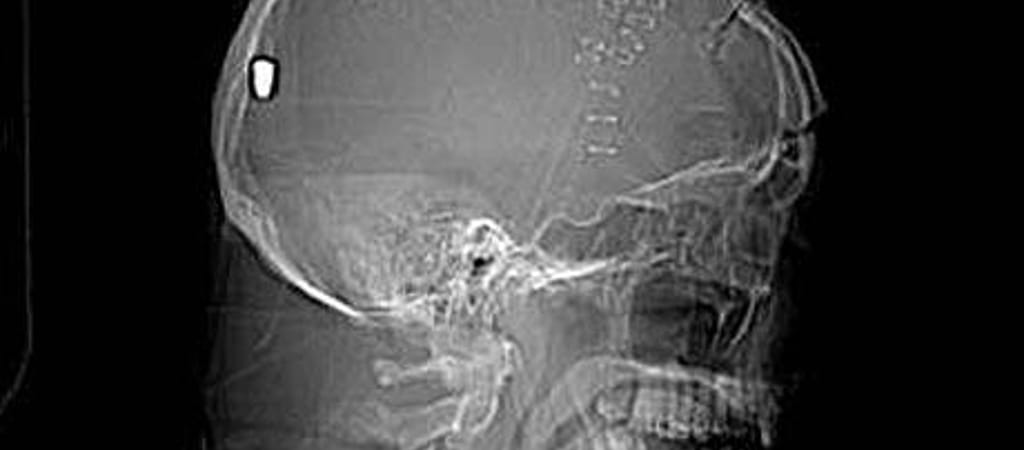

Tanúkat keres a manchesteri rendőrség a 61 éves Peter Hesford ügyében, aki kertészkedés közben szerzett szemsérülésével került kórházba a múlt hónapban. A röntgenfelvételek egy pisztolygolyót mutattak ki a férfi koponyájában, amely a ballisztikai szakértők szerint a szemén keresztül hatolhatott be az agyába.

A jelenleg súlyos, de stabil állapotban lévő férfi chorltoni otthona mellett, kertészkedés közben esett össze és nem emlékszik, mi történt vele. A kórházban elvégzett CT-vizsgálat kiderítette, hogy egy tárgy hatolt be az agyába – a későbbi vizsgálatok során kiderült, hogy a koponya hátsó részében felfedezett tárgy egy lövedék, amely a férfi szemén keresztül kerülhetett oda.

A manchesteri rendőrség – amely közzétette a férfi koponyájáról készült röntgenképet is – most azt kéri, hogy jelentkezzen, aki tud valamit az esetről, vagy Hesford háza környékén tanúja volt bármilyen szokatlan eseménynek - közölte a BBC.